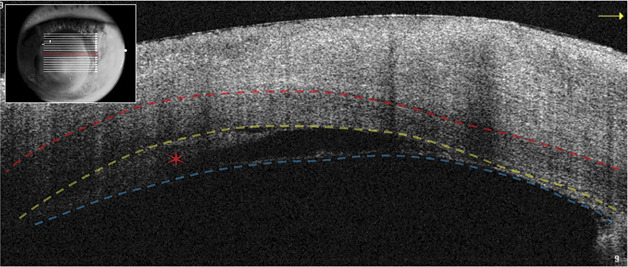

Diagnosis intervention and outcomes: Anterior segment optical coherence tomography (AS-OCT) identified an intracorneal hypopyon between the Descemet membrane and corneal stroma of the DSAEK graft. Antibiotics were continued, while topical steroids, initially reduced in response to infection, were increased modestly. The patient's condition and hypopyon gradually improved.

Conclusions: Ophthalmologists should consider the possibility of an intracorneal hypopyon masquerading as a persistent stromal infiltrate in the setting of infectious keratitis. Unlike unresponsive corneal infiltrates, intracorneal hypopyons may represent sterile inflammatory debris after resolved infection. AS-OCT was critical to distinguish the intracorneal hypopyon from a persistent infiltrate, which may have prevented unnecessary and/or invasive interventions.